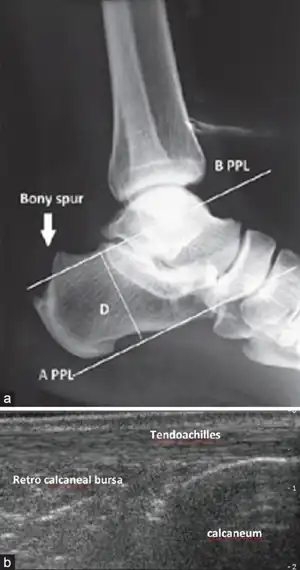

| Preoperative X-ray ankle joint lateral view showing (a) the parallel pitch lines (PPLs) determine the prominence of the bony projection. (b) Ultrasound ankle showing Achilles tendon, tetrocalcaneal bursa, and calcaneum | |

Retrocalcaneal bursitis is an inflammation of the bursa located between the calcaneus and the anterior surface of the Achilles tendon.[1] It commonly occurs in association with rheumatoid arthritis, spondyloarthropathies, gout, and trauma.